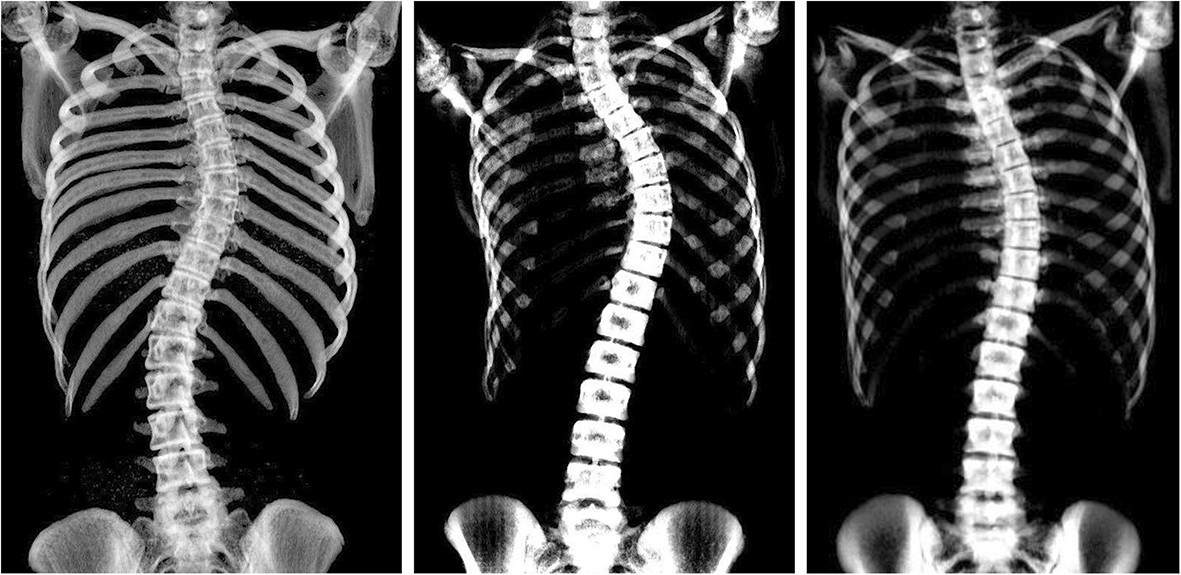

يُعدّ اعوجاج العمود الفقري المراهقي مجهول السبب (Adolescent Idiopathic Scoliosis – AIS) من أكثر اضطرابات الظهر شيوعًا خلال مرحلة النمو بين سن 10 و16 عامًا. وبالتالي، فإن كثيرًا من الحالات تتطلب متابعة دقيقة لمنع التدهور. وفي هذه الحالات، يكون حزام اعوجاج العمود الفقري الوسيلة الأهم لتقويم الانحناء والحد من الحاجة للجراحة. ومع ذلك، تختلف استجابة المراهقين للحزام بشكل كبير، ولذلك تظهر أهمية استخدام أدوات حديثة تساعد في توقّع نتائج العلاج قبل البدء به.

اعتمد الباحثون على دراسة كبرى شملت 207 مراهقين مصابين باعوجاج العمود الفقري، بمتوسط عمر 12.8 سنة.

وخلال هذه الدراسة، تم قياس مجموعة من المؤشرات الأساسية، وهي:

زاوية كوب (Cobb Angle) قبل العلاج

مرونة العمود الفقري أثناء الاستلقاء

نسبة التصحيح التي يحققها الحزام فور ارتدائه

معدل الالتزام اليومي بالحزام

مرحلة النمو العظمي (Risser – Sanders)

متابعة الحالة حتى انتهاء العلاج أو الحاجة للجراحة

وبناءً على هذه البيانات، وُضع مؤشر SCI كأداة جديدة تساعد في التنبؤ بنتائج الحزام بدقة عالية.